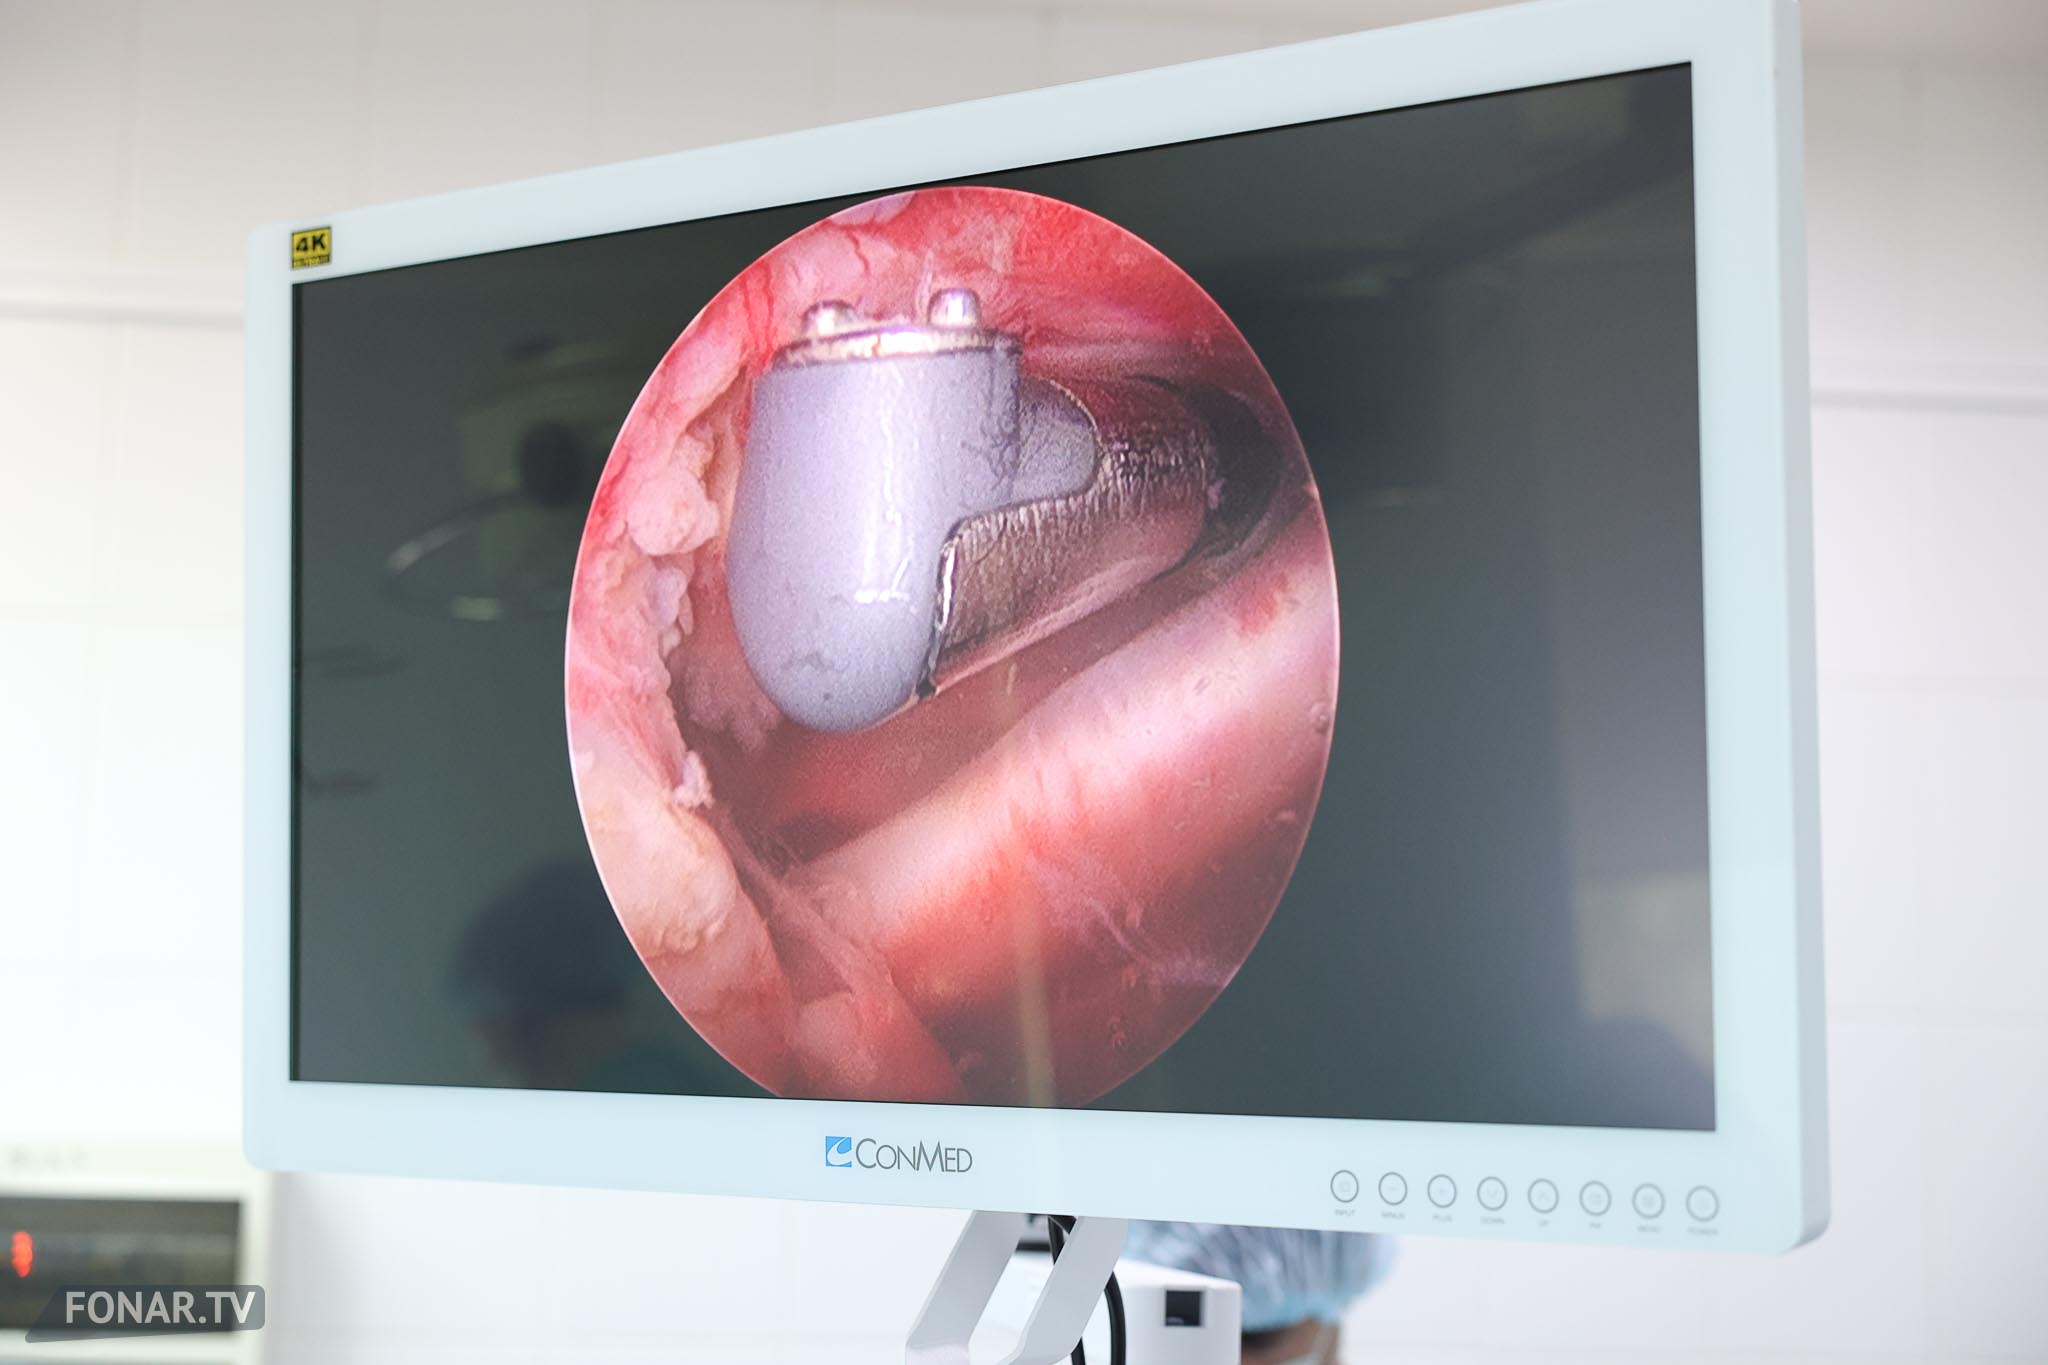

— Это малотравматичное вмешательство, оно выполняется под анестезией. Через прокол мы входим в плечевой сустав, визуализируем на экране повреждения. Сустав не вскрывается полностью — работа идёт через проколы. Выполняется шов повреждённых сухожилий, восстановление анатомических структур. В частности — шов ротаторной манжеты, восстановление суставной губы.

Это целая группа операций, объединённых в так называемую «артроскопическую» хирургию. В неё входит множество методик. Мы внедряем не одну конкретную процедуру, а целый спектр артроскопических операций, которые позволяют лечить широкий круг патологий.